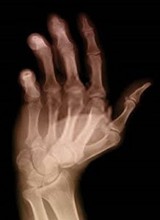

Artritis cura con Bórax  Dolores

de articulaciones por artritis curan con Bórax  Osteoporosis cura con bórax  Caries

es reducica con bórax

Artritis cura con bórax [3] - dolores de articulaciones por artritis curan con bórax [4] - osteoporosis cura con bórax [5] - caries es reducica con bórax [6] -